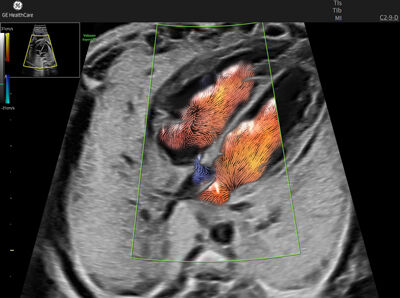

SMI G4 (Superb Microvascular Imaging): visualizzazione avanzata della microvascolarizzazione

Advanced Doppler per flussi lenti e microvascolarizzazione